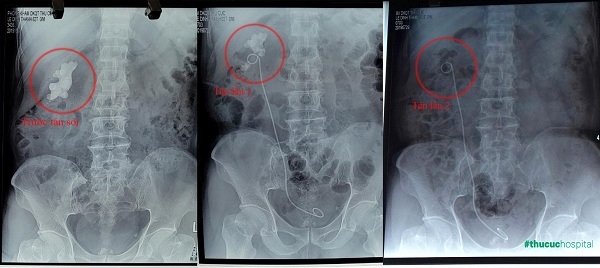

Tán sỏi ngoài cơ thể tối ưu cho các trường hợp sỏi thận Các trường hợp sỏi có kích thước lớn không thể tán ngoài cơ thể hiện nay cũng đã có cách tán sỏi rất ít gây xâm lấn. Cách đây không lâu bệnh viện đã điều trị thành công một ca sỏi san hô 7cm, chiếm gần hết đài bể thận bằng phương pháp tán sỏi nội soi qua da đường hầm nhỏ. Sau tán bệnh nhân chỉ có một vết trích 5mm trên vùng thắt lưng hông.”

Sỏi thận “khủng” 7cm được làm sạch sau 2 lần tán sỏi nội soi qua da đường hầm nhỏ với 1 vết trích siêu nhỏ.